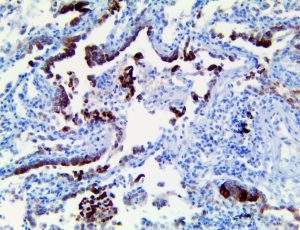

The first cytokines released are interleukin 1β (IL-1β) and tumor necrosis factor-α (TNF-α), which attract a variety of circulating white blood cells (WBCs) to the infection site, including neutrophils, monocytes, macrophages, and natural killer (NK) cells. This response, along with the antipathogenic chemicals released by these cells (i.e., complement), comprise the innate immune response. These cells directly attack the invading pathogen and also release additional cytokines, chief among them interleukin-1 and 6 (IL-6). IL-6 is essential for invoking the adaptive immune response, which calls T-cells, B-cells, and T helper (Th) cells to the infection site. IL-6 also stimulates further recruitment, proliferation and activation of macrophages.

It is the ICU physician who is most likely to witness one of the deadliest manifestations of the abnormal immunological response, the cytokine storm syndrome (CSS). This response is also referred to by some as the cytokine release syndrome (CRS). CSS is characterized by continuous activation and expansion of macrophage and lymphocyte populations, which secrete large amounts of cytokines, causing the cytokine storm. This massive cytokine release is akin to hemophagocytic lymphohistiocytosis (HLH) disease, a syndrome characterized by initial unchecked and persistent activation of cytotoxic T lymphocytes and NK cells.

Clinical and laboratory manifestations of HLH include fever, enlarged liver and/or spleen, neurologic dysfunction, coagulopathy, liver dysfunction, cytopenias (i.e., low levels of erythrocytes, leukocytes, and/or platelets), hypertriglyceridemia, hyperferritinemia, hemophagocytosis, and eventually diminished NK cell activity as the immune system becomes progressively paralyzed. HLH can be familial (primary HLH) or secondary to another disease process (sHLH), such as rheumatic disease, in which it is referred to as macrophage activation syndrome (MAS, characterized by elevated ferritin).